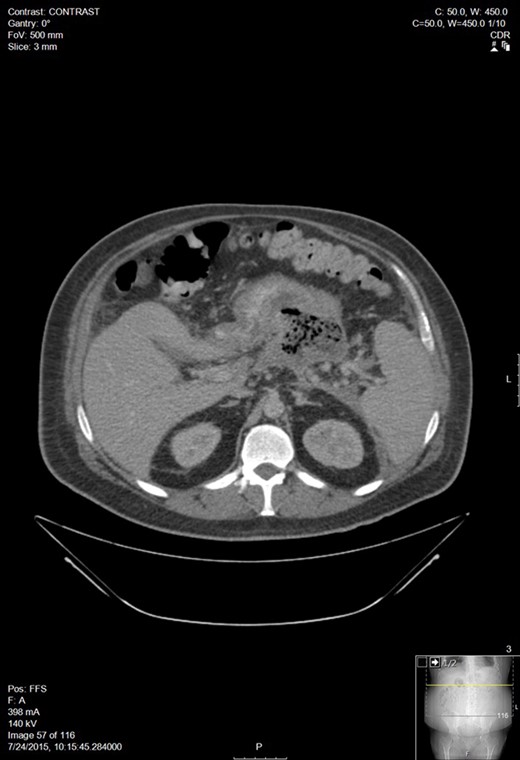

A 30-year-old man with a past medical history of hypertriglyceridemia presented to an outside ER with nausea, vomiting and abdominal pain. Lab studies were significant for pancreatitis (lipase 2730), hypertriglyceridemia (1594), blood glucose of 389 and BUN/Cr of 17/1.3. A CT of the abdomen showed AP. A subsequent lab draw showed BUN/Cr to 27/3.8, decrease in lipase to 565, increase in triglycerides to 4243, and a BNP 15. He was transferred to our facility following worsening hypoxemia. A CT scan was performed: representative sections shown below demonstrated walled off pancreatic necrosis (Fig. 1). He was in acute renal failure on presentation and started on continuous renal replacement therapy. The renal failure resolved, he completed a 7-day course of imipenem/cilistatin and was eventually discharged 11 days after admission.

Worsening walled off pancreatic necrosis with extension to the paracolic gutters.